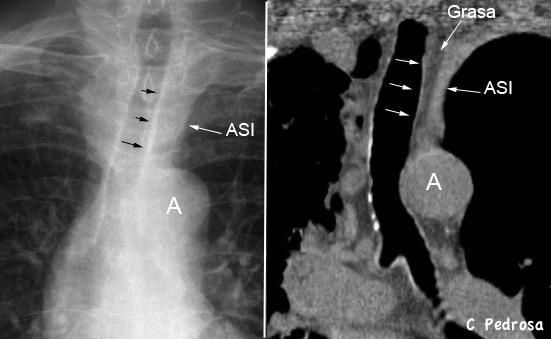

62. LÍNEAS PARAESPINALES. DESPLAZAMIENTO BILATERAL DE

Líneas paraespinales formando un “paréntesis” por encima del diafragma. El signo señala el origen “intratorácico” de la lesión.

Conrad A et al. Pott’s disease associated with large and multiple abscesses in a 30-year-old migrant from Chad. BMJ Case Rep 2018

(lesiones toracoabdominales) La divergencia de las líneas paraespinales apunta a lesión toracoabdominal, que desde el tórax desciende y penetra en el abdomen.

Signo del “iceberg” positivo en Tb vertebral